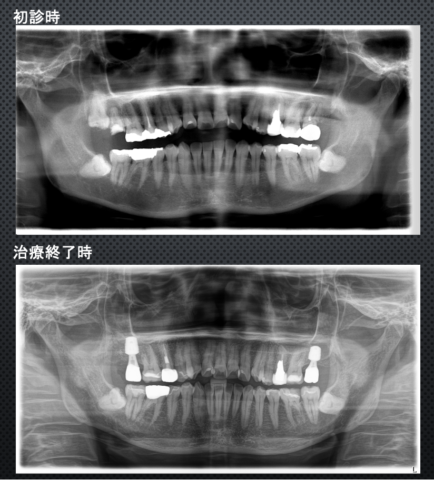

パノラマレントゲン比較